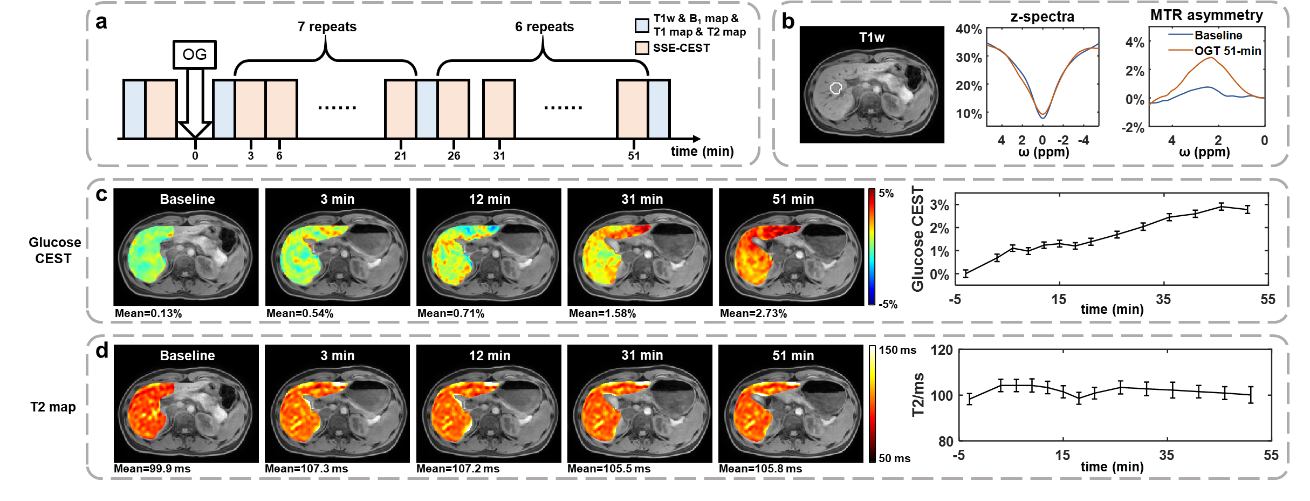

3、口服葡萄糖动态代谢成像

在OGTT实验中,SSE-CEST连续监测至服葡萄糖后51分钟,肝脏MTRasym(2.1 ppm)信号在30分钟左右达到平台期,而T2变化不显著,证明了SSE-CEST对葡萄糖代谢的特异性检测能力(图5)。

图5 SSE-CEST 技术在OGTT实验中用于动态葡萄糖成像